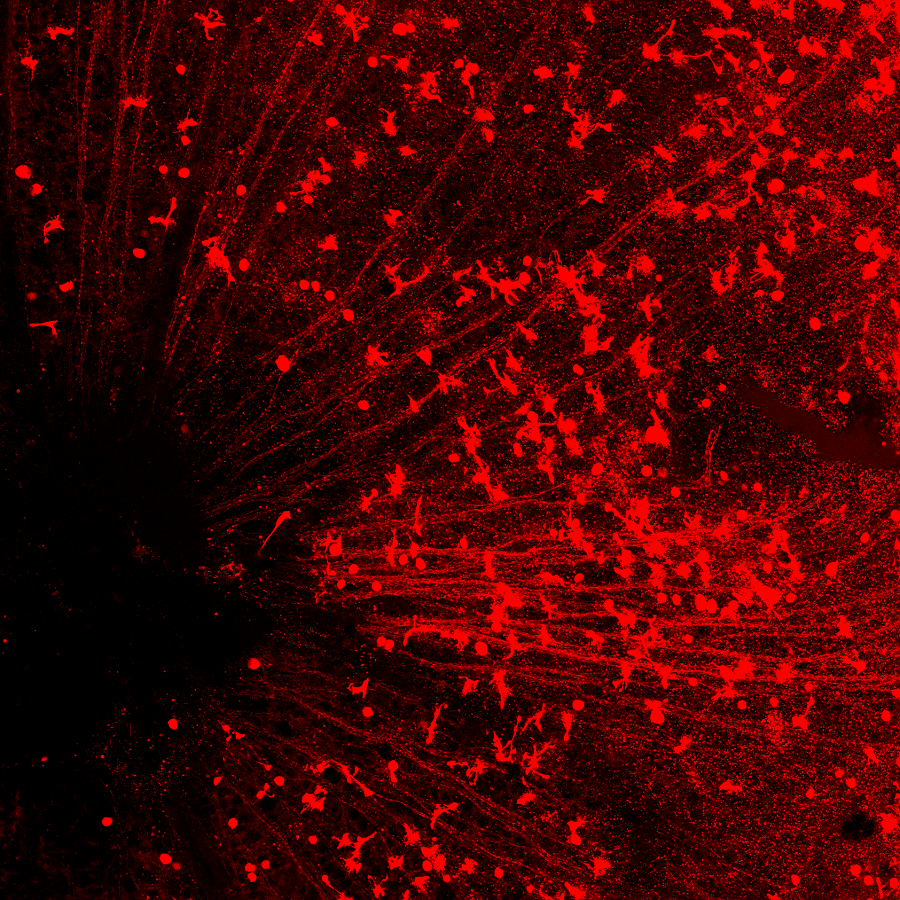

在小鼠的視網(wǎng)膜上,紅色圓形的細(xì)胞是再生出的視神經(jīng)節(jié)細(xì)胞,可以看到一條一條的紅線匯集到眼睛中間的視盤(左下黑洞區(qū)域),這是再生出的視神經(jīng)節(jié)細(xì)胞發(fā)出的軸突,它們將通過視盤傳到視神經(jīng),然后再到大腦。

視神經(jīng)部位是連接眼睛和大腦的橋梁。每一條紅色的線是每一個(gè)再生出來的視神經(jīng)節(jié)細(xì)胞發(fā)出的軸突,通過這里,這些新生軸突將會(huì)與大腦中處理視覺信號(hào)的區(qū)域正確相連。